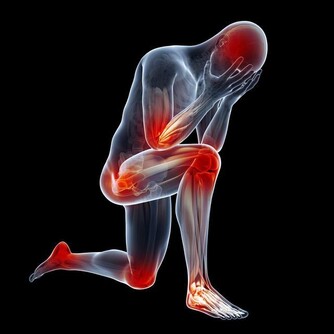

動脈硬化、高血壓

引起的眼部變化主要是眼底血管的改變,表現為眼底微血管變細、扭曲、滲出,甚至血管破裂、出血,會造成患者視力下降或突發性看不見東西。主要防治辦法就是控制血壓、血脂。所以,中老年人的飲食,應貫徹低脂、低鹽、低糖的原則,重視對動脈硬化和高血壓的防治。檢查身體時不要忘記檢查眼底。